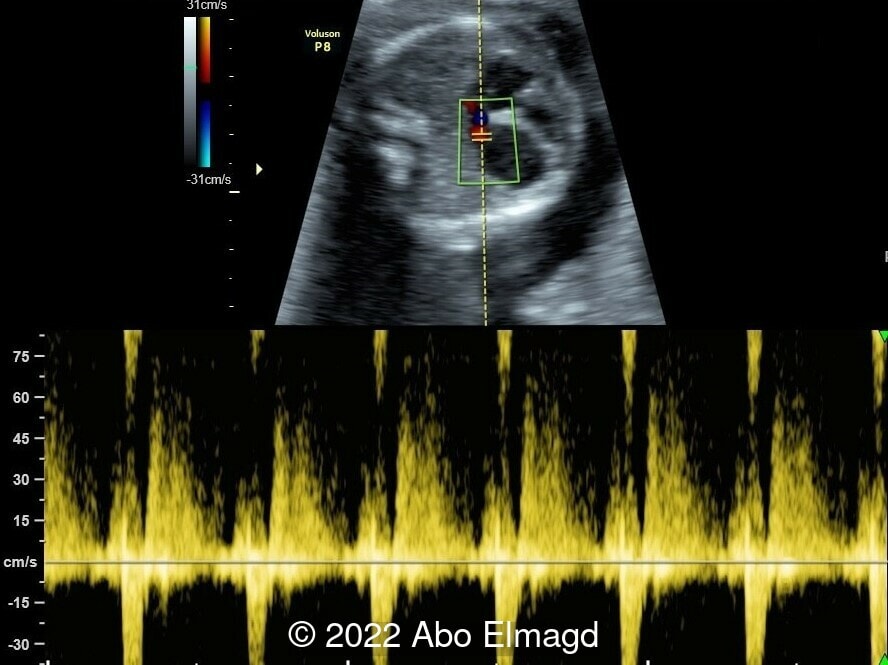

Image 2: Reduced filling of the left ventricle with stagnant blood flow due to poor contractility.